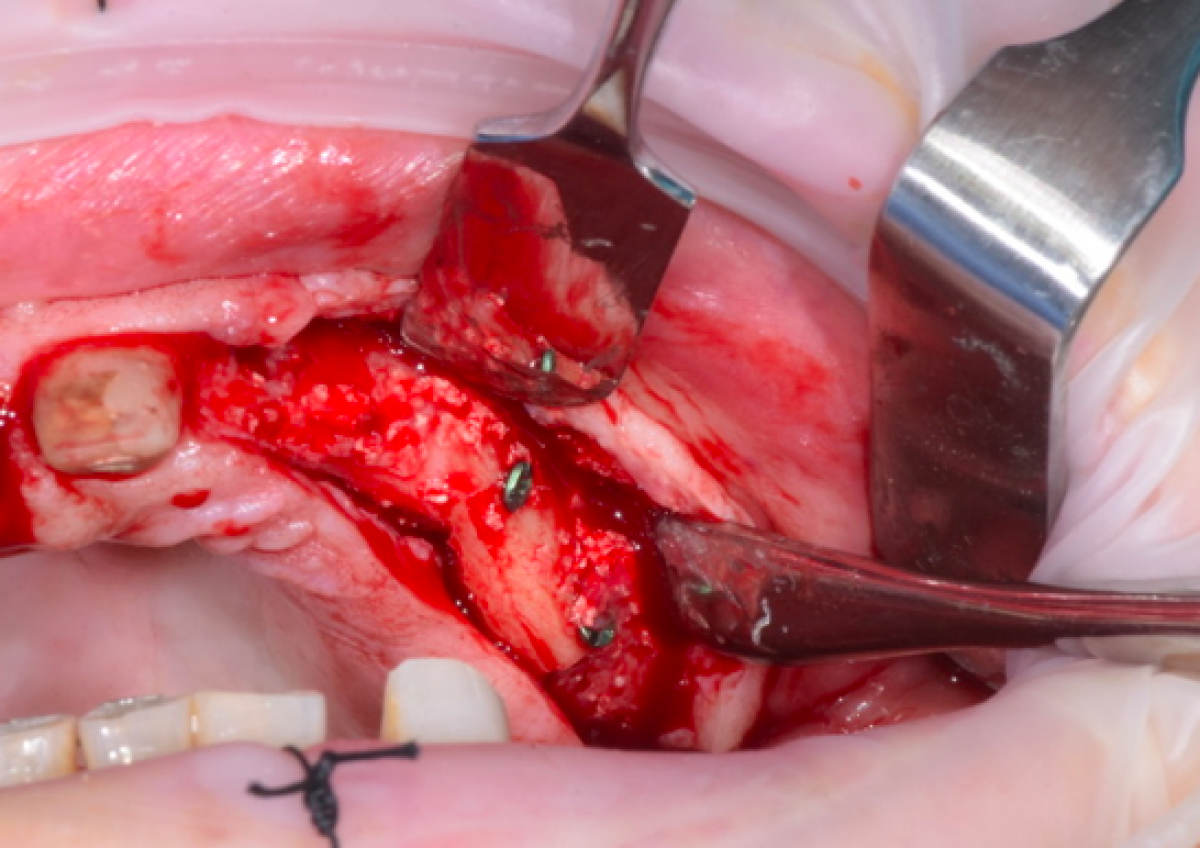

After isolating the entire quadrant with rubber dam, a FenderWedge (Directa) was positioned between the elements 2.4 and 2.5, ie a plastic wedge equipped with a steel insert which, in addition to protecting the dam and gently separating the teeth, prevents damage to tooth 2.4 during cavity preparation of tooth 2.5. The FenderWedge was inserted with the help of a dental tweezer and selected from 4 different sizes to ensure the correct separation between two contiguous elements, up to the marginal ridge. The latter is not demolished initially but access to the lesion is obtained by opening the cavity towards the center of the tooth. (Figure 2)